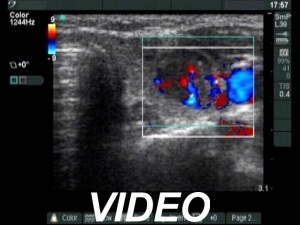

Ultrasonography: There were three hypoechogenic lesions wich has hyperechogenic granules larger than foci of microcalcification. There was a lymph node above the left lobe. The node lacked a regular hilum and was round

Comment. The coarse and large hyperechogenic figures seen on ultrasonography correspond to amyloid deposits. In contrast with coarse calcification, there is no acoustic shadow dorsal to amyloid. The foci of amyloid are much larger than a microcalcification. The specificity of this type of hyperechogenic figures is around 50%.